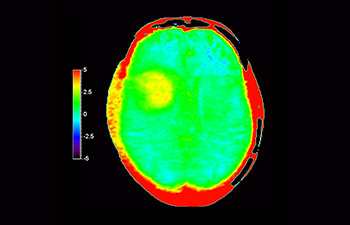

In a society where neurological disorders represent a heavy burden, Philips is committed to provide superb diagnostic clarity and treatment guidance for all patients. Today, although MR is the gold standard in neuro oncology imaging, its accuracy in tumor grading and treatment follow up assessment can be further improved. 3D APT (Amide Proton Transfer) is a unique, contrast-free, brain MR imaging method addressing the need for more confident diagnosis in neuro oncology. 3D APT uses the presence of endogenous cellular proteins, to produce an MR signal that directly correlates with cell proliferation, a marker of tumoral activity. 3D APT can support trained medical professionals in differentiating low grade from high grade gliomas and, in differentiating tumor progression from treatment effect1.